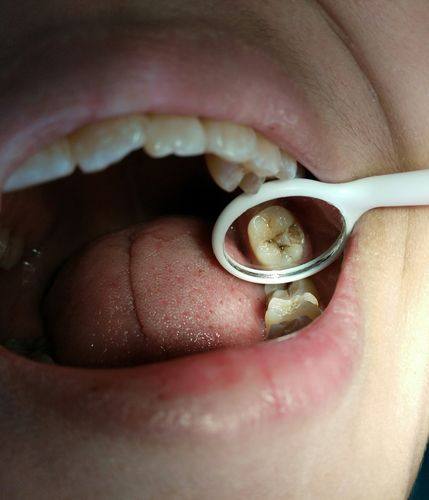

口腔局部感染重度的儿童

当孩子口腔局部感染重度时,也不适合马上补牙。比如牙齿周围有重度的牙龈脓肿、根尖周炎等情况。在感染没有得到有效控制的情况下补牙,可能会导致感染进一步扩散,加重病情。此时,应该精良行抗感染治疗,等炎症消退后,再进行补牙。这样可以确保补牙的成效,也能避免感染对孩子口腔健康造成更重度的影响。